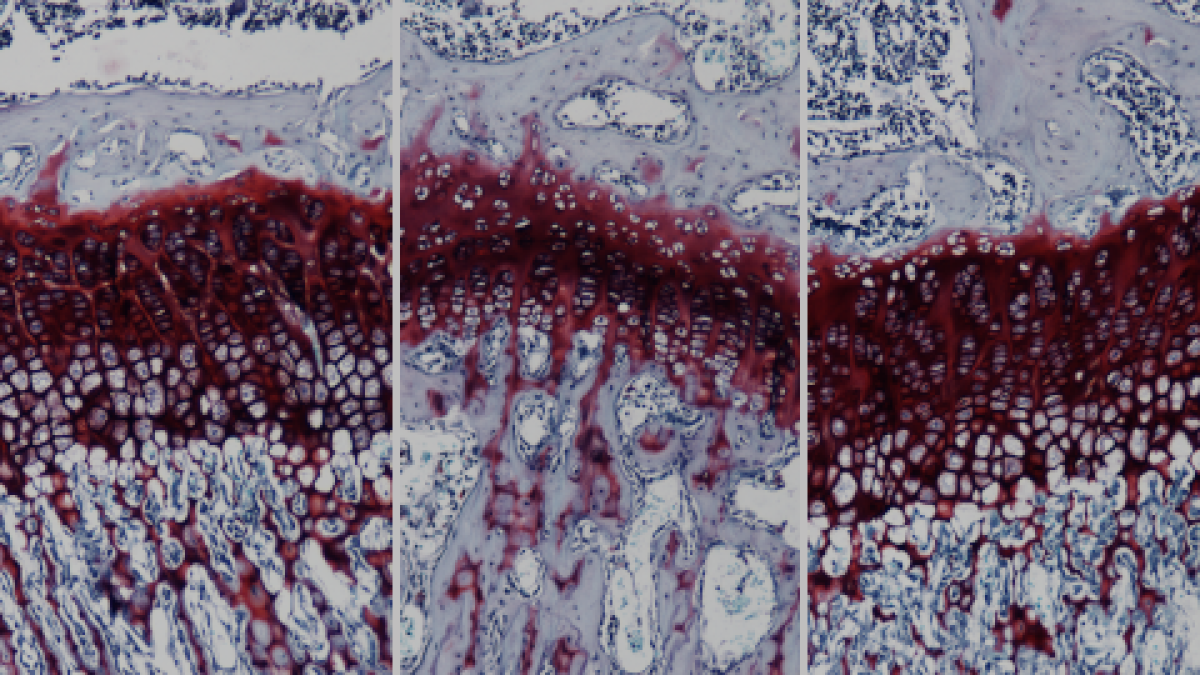

A continuación, y por primera vez, los investigadores han conseguido curar completamente los animales mediante el desarrollo de una terapia génica basada en la administración de un vector viral que codifica por la enzima GALNS. Una sola inyección intravenosa del vector viral permite la biodistribución y expresión ubicua del gen terapéutico, sobre todo a nivel de todo el sistema esquelético. Eso, permite recuperar a largo plazo la producción de la enzima en el esqueleto del animal, evitando las alteraciones en los huesos, y también en los cartílagos, la tráquea y el corazón.

«La administración de la terapia génica en ratas modelo de tan sólo cuatro semanas revierte completamente los efectos de la enfermedad, las alteraciones en el crecimiento de los huesos, las malformaciones y fragilidad de los dientes, las patologías en los cartílagos de las articulaciones, así como las complicaciones cardiorrespiratorias debidas a las afectaciones en la tráquea y en el corazón,» explica la investigadora de la UAB Fàtima Bosch, directora del estudio.